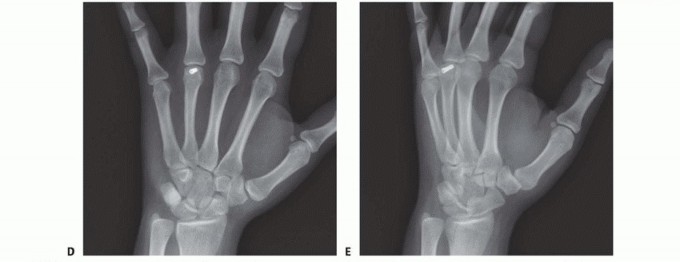

When standard radiographs are equivocal, or when dealing with complex intra-articular fractures and suspected CMC fracture-dislocations, advanced cross-sectional imaging is mandatory. High-resolution Computed Tomography (CT) with 3D reconstructions provides unparalleled detail of articular step-offs, occult comminution, and the precise spatial orientation of fracture fragments. This information is invaluable for determining the feasibility of lag screw fixation versus the necessity of bridge plating. Furthermore, obtaining radiographs of the uninjured, contralateral hand serves as a vital anatomical template, allowing the surgeon to accurately gauge the patient's native metacarpal length and intrinsic diaphyseal curvature.

Clinical & Radiographic Imaging Archive